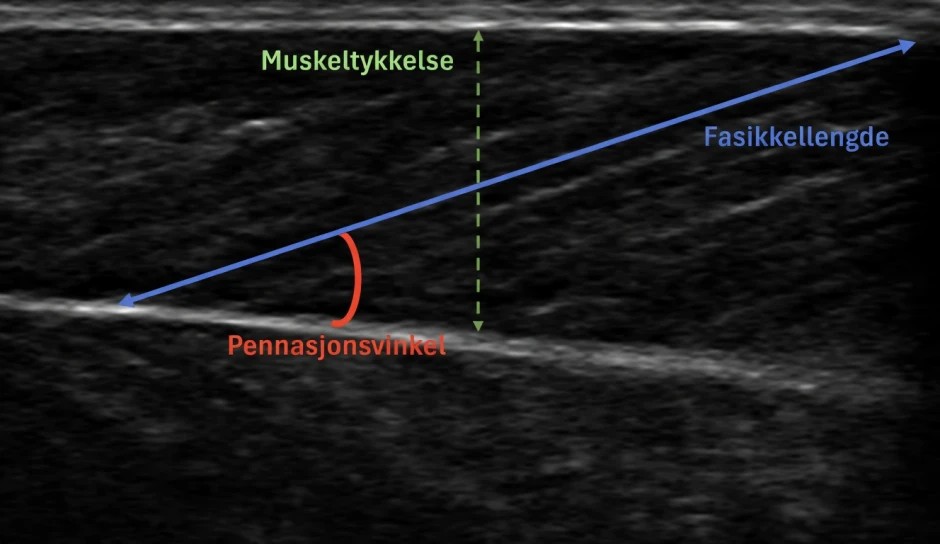

Muskelarkitektur, det vil si hvordan muskelfibrene er arrangert i muskelen, kan ha stor betydning for både kraftproduksjon og energikostnad. Dette kan til og med være uavhengig av muskelens størrelse (Fletcher & MacIntosh, 2017; Van Hooren et al., 2024) Når man diskuterer muskelarkitektur diskuteres ofte fasikkellengde (lengden på muskelfibrene) og pennasjonsvinkel (vinkelen mellom muskelfibrene og senens kraftretning: se figur 1).

Figur 1. Viser muskeltykkelse, fasikkellengde, og pennasjonsvinkel i muskelen medial gastrocnemius målt.